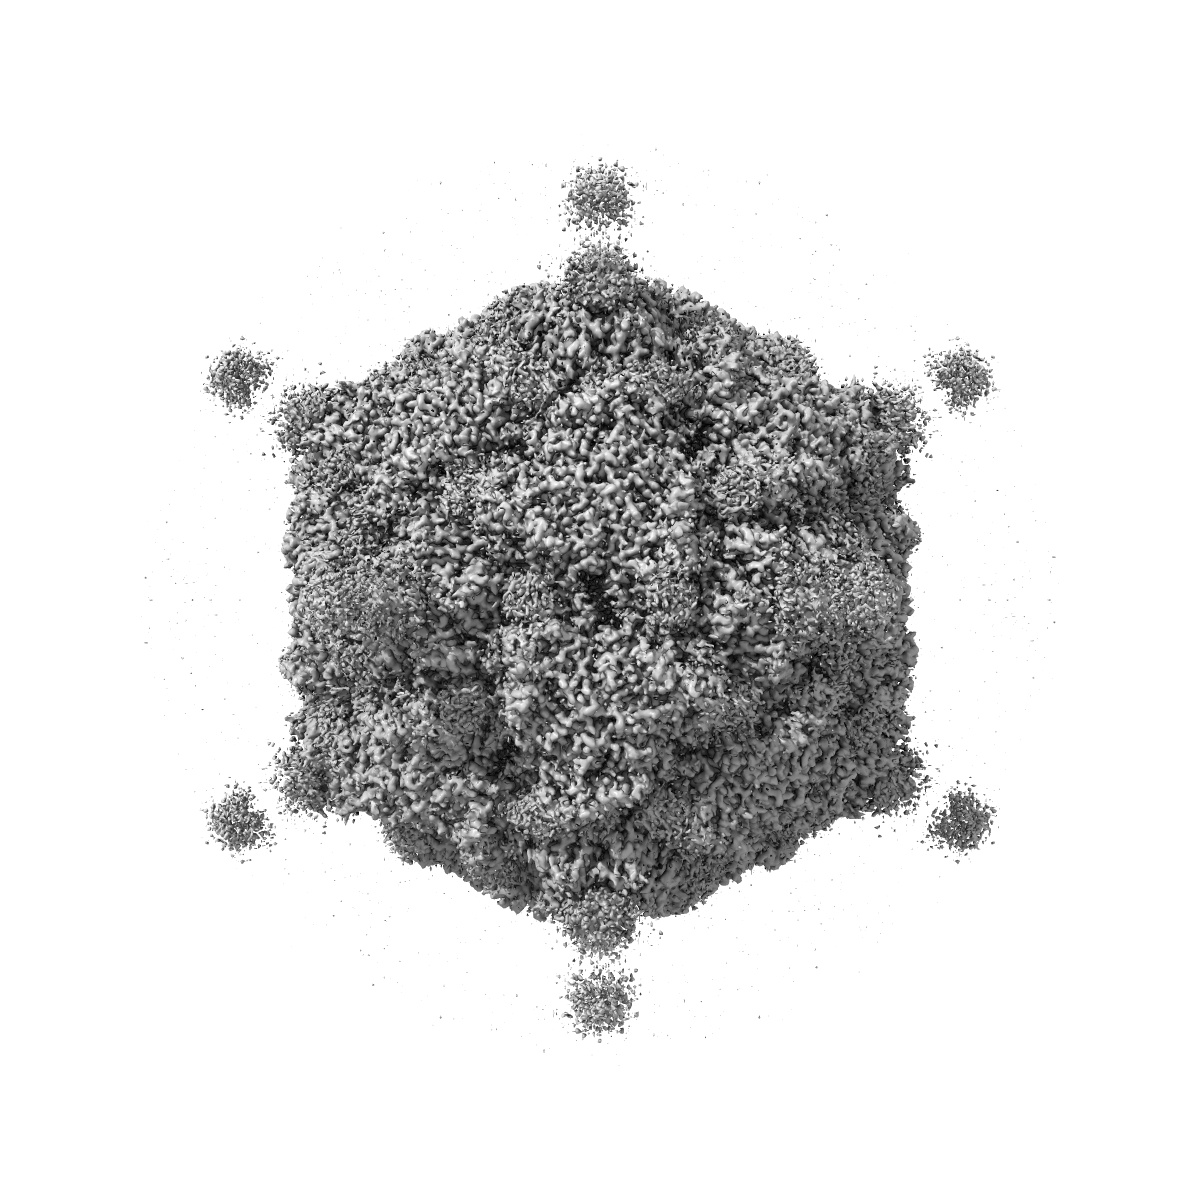

EMD-0891

The cryo-EM structure of coxsackievirus A16 A-particle in complex with Fab 18A7

Single-particle3.07 Å